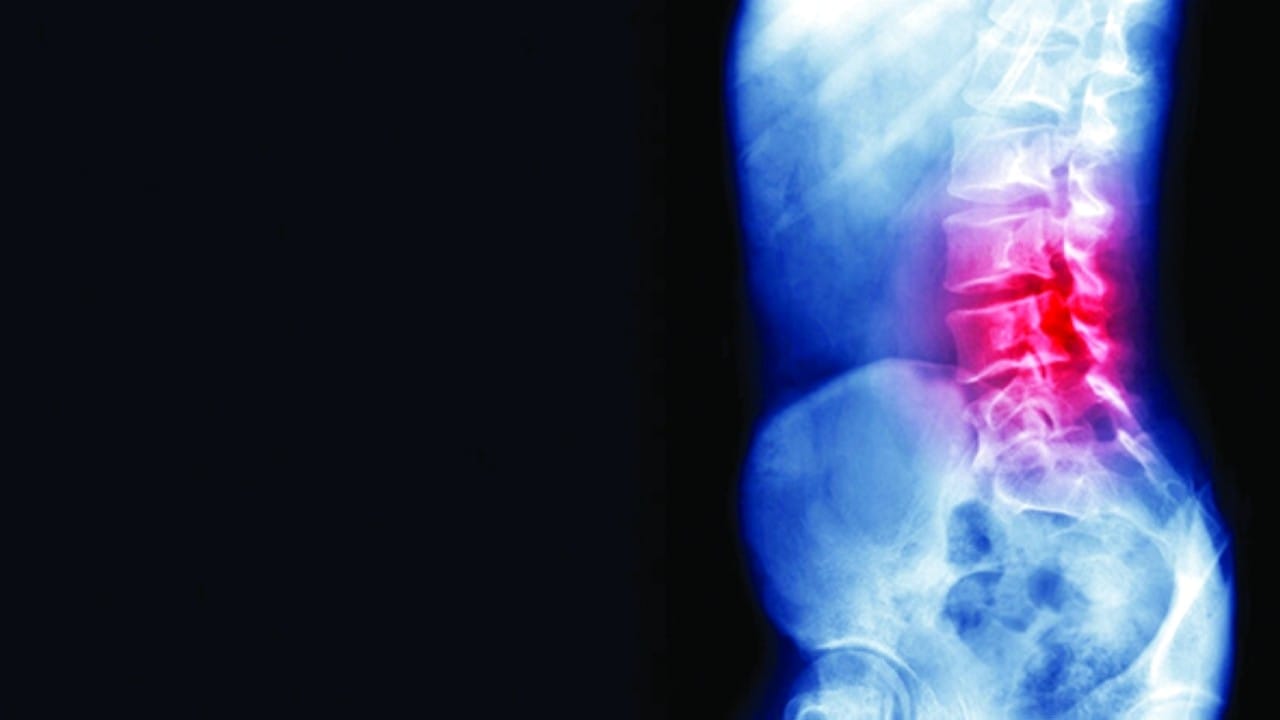

غاز الضحك يدمر العمود الشوكي لرجل